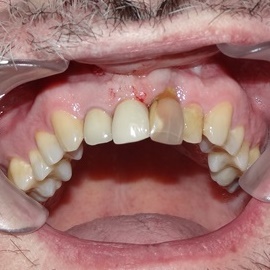

Lat 50, pół roku przed rozpoczęciem leczenia implantologicznego przestał palić papierosy. Znacząca poprawa higieny, pacjent silnie zmotywowany. Po regeneracji kości i rekonstrukcji tkanek miękkich odbudowa sześciu zębów na koronach porcelanowych. Na zdjęciu widoczna ilość i jakość tkanki kostnej po rekonstrukcji. W porównaniu ze stanem początkowym uzyskano znaczącą poprawę warunków kostnych nie do osiągnięcia metodami sterowanej regeneracji kości z użyciem reklamowanych markowych błon kolagenowych i dosypaniem kości z butelki.